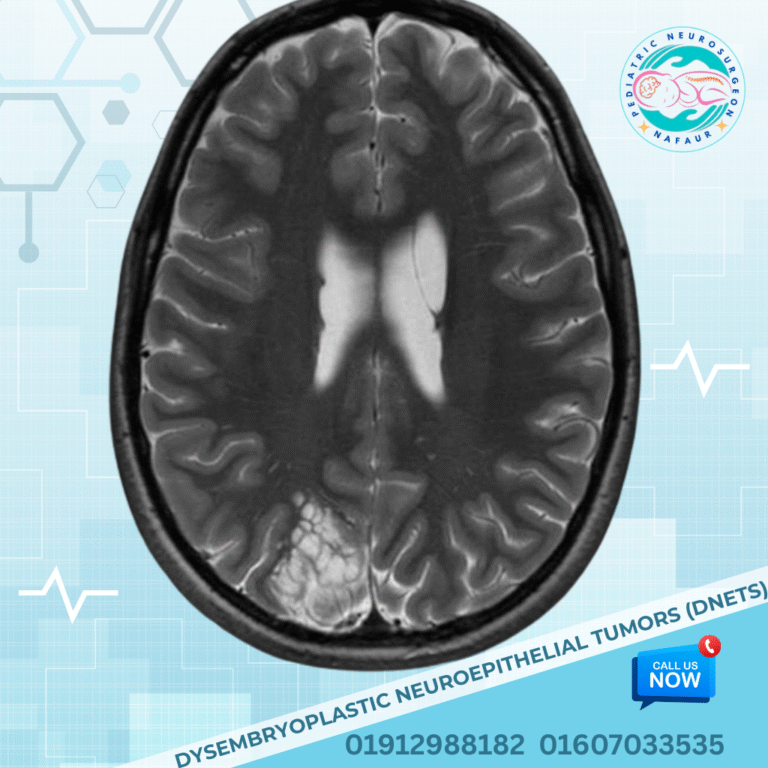

Dysembryoplastic Neuroepithelial Tumors (DNETs)

Often presents with seizures; benign but may need excision for epilepsy control